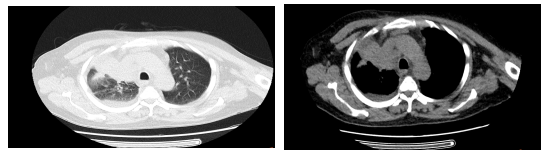

2025年2月7日,阿坝州人民医院呼吸与危重症医学科接诊了一位68岁的男性患者。这位患者因“咳嗽、咳痰、气紧1周”而入院,经过初步的胸部CT(平扫+增强)检查,结果显示其右肺上叶存在占位性病变,考虑肺癌的可能性较大。然而,由于病灶位置靠近外侧,远离主支气管,传统的气管镜检查无法获取病原学及病理诊断,这无疑给患者的治疗带来了极大的挑战。

穿刺前,患者的CT影像清晰地显示了病灶的位置和形态,为手术提供了重要的参考依据。